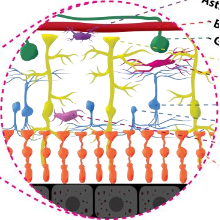

Kowalczuk L., Dornier R., Navarro A., Jeunet F., Moser C., Behar-Cohen F., Mantel I., Adaptive Optics-Transscleral Flood Illumination Imaging of Retinal Pigment Epithelium in Dry Age-Related Macular Degeneration, Cells (2025), 14(9), 633. doi: 10.3390/cells14090633. |

Govindahari V., Dornier R., Ferdowsi S., Moser C., Mantel I., Behar-Cohen F., Kowalczuk L., High-Resolution Adaptive Optics-Trans-scleral Flood Illumination (AO-TFI) Imaging of Retinal Pigment Epithelium (RPE) in Central Serous Chorioretinopathy (CSCR), Scientific Reports, 14.1 (2024):13689. doi: 10.1038/s41598-024-64524-4. |

Leong F., Rahmani B., Psaltis D., Moser C., Ghezzi D., An actor-model framework for visual sensory encoding, Nature Communications 15.1 (2024). doi: 10.1038/s41467-024-45105-5. |

Kowalczuk L., Dornier R., Kunzi M., Iskandar A., Misutkova Z., Gryczka A., Navarro A., Jeunet F., Mantel I., Behar-Cohen F., Laforest T., Moser C., in vivo Retinal Pigment Epithelium Imaging using Transscleral OPtical Imaging in healthy eyes, Ophthalmology Science, 100234 (2022). |

dos Santos F., Laforest T., Künzi M., Kowalczuk L., Behar-Cohen F., and Moser C., Fully automated detection, segmentation, and analysis of in vivo RPE single cells, Eye, June 2020. |

Laforest T., Künzi M., Kowalczuk L., Carpentras D., Behar-Cohen F. and Moser C. , Transscleral optical phase imaging of the human retina, Nature Photonics, March 2020. |